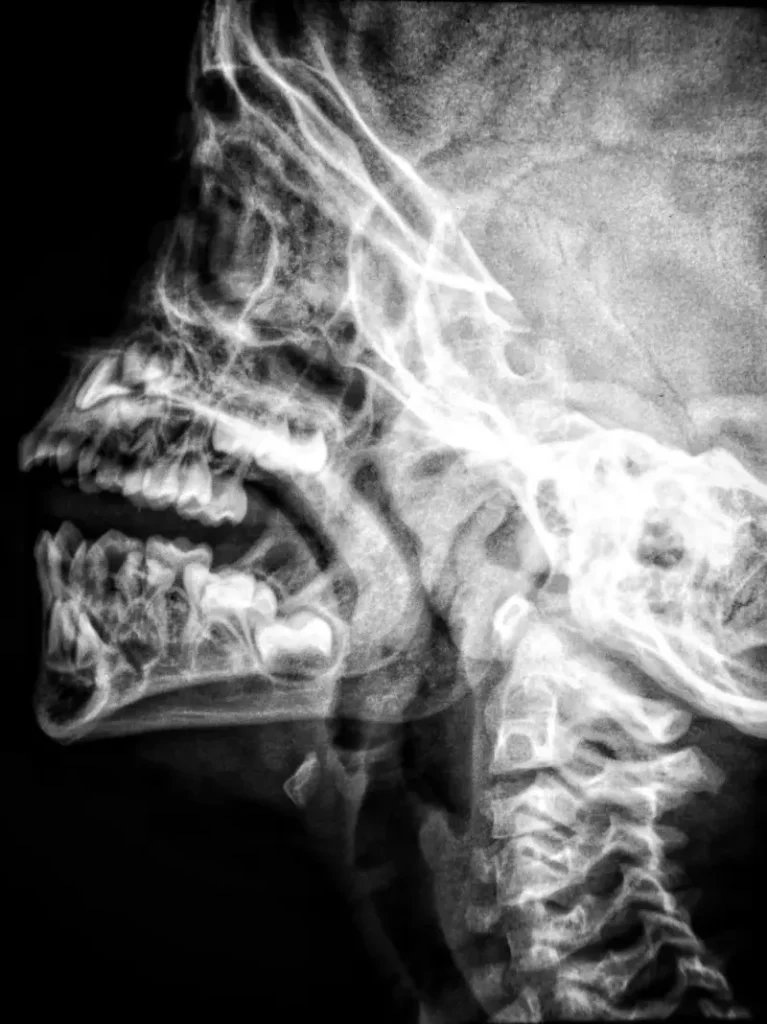

Teleradiologia

Teleradiologia to dziedzina medycyny, która wykorzystuje technologię telekomunikacyjną do przesyłania obrazów radiologicznych, m.in.:

• zdjęcia rentgenowskie,

• tomografie komputerowe,

• rezonanse magnetyczne i inne.